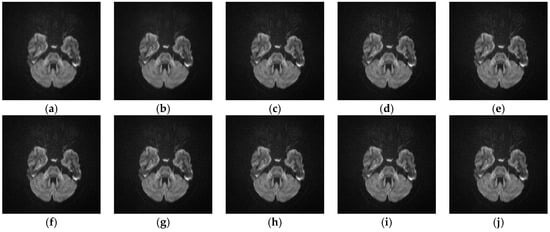

5.2.4. Analyze the Performance of Different SR Algorithms on Real Medical Images